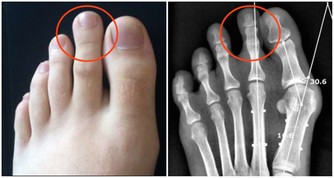

血管堵塞的症狀

2、 四肢腫脹疼痛

四肢肢是人體供血的最末端,當血管堵塞後,四肢的供血和回血不足就會出現腫脹現象。四肢組織處於缺血缺氧狀態下就會伴隨有疼痛的表現,特別是靜脈血栓發生後,腫脹症狀更為明顯。